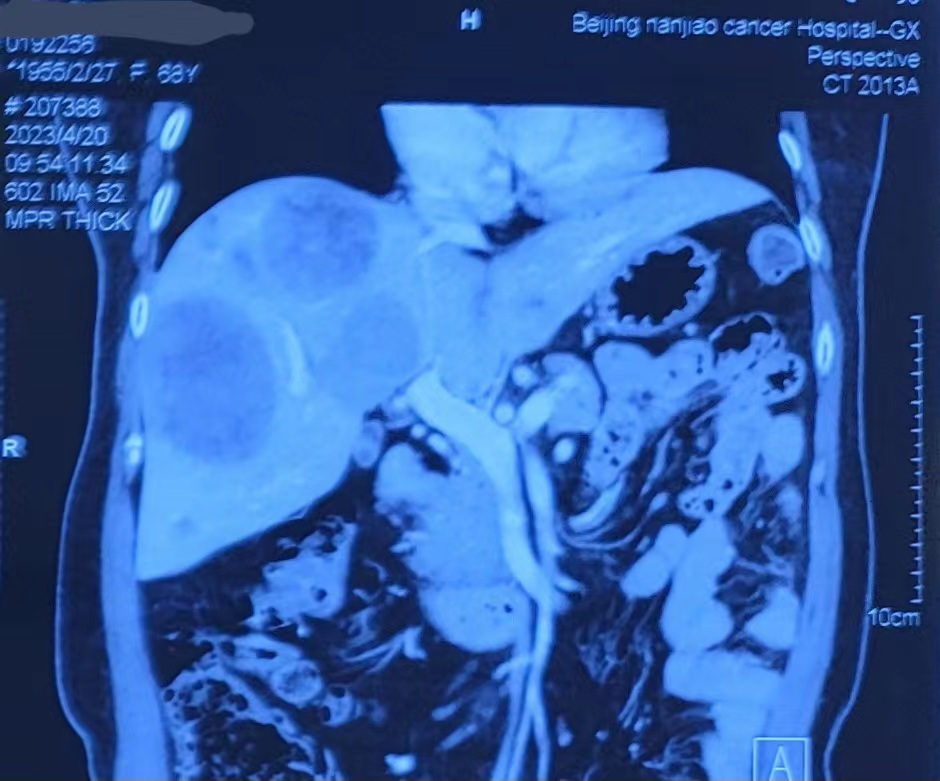

Progress of intrahepatic lesions shown on the abdominal CT after admission to our hospital.